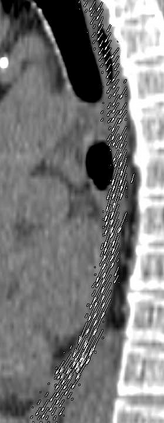

Stereotactic body radiation therapy allows for a precise and accurate dose delivery. Organ motion during treatment bears the risk of undetected high dose healthy tissue exposure. An organ very susceptible to high dose is the oesophagus. Its low contrast on CT and the oblong shape renders motion estimation difficult. We tackle this issue by modern algorithms to measure the oesophageal motion voxel-wise and to estimate motion related dosimetric impact. Oesophageal motion was measured using deformable image registration and 4DCT of 11 internal and 5 public datasets. Current clinical practice of contouring the organ on 3DCT was compared to timely resolved 4DCT contours. The dosimetric impact of the motion was estimated by analysing the trajectory of each voxel in the 4D dose distribution. Finally an organ motion model was built, allowing for easier patient-wise comparisons. Motion analysis showed mean absolute maximal motion amplitudes of 4.24 +/- 2.71 mm left-right, 4.81 +/- 2.58 mm anterior-posterior and 10.21 +/- 5.13 mm superior-inferior. Motion between the cohorts differed significantly. In around 50 % of the cases the dosimetric passing criteria was violated. Contours created on 3DCT did not cover 14 % of the organ for 50 % of the respiratory cycle and the 3D contour is around 38 % smaller than the union of all 4D contours. The motion model revealed that the maximal motion is not limited to the lower part of the organ. Our results showed motion amplitudes higher than most reported values in the literature and that motion is very heterogeneous across patients. Therefore, individual motion information should be considered in contouring and planning.